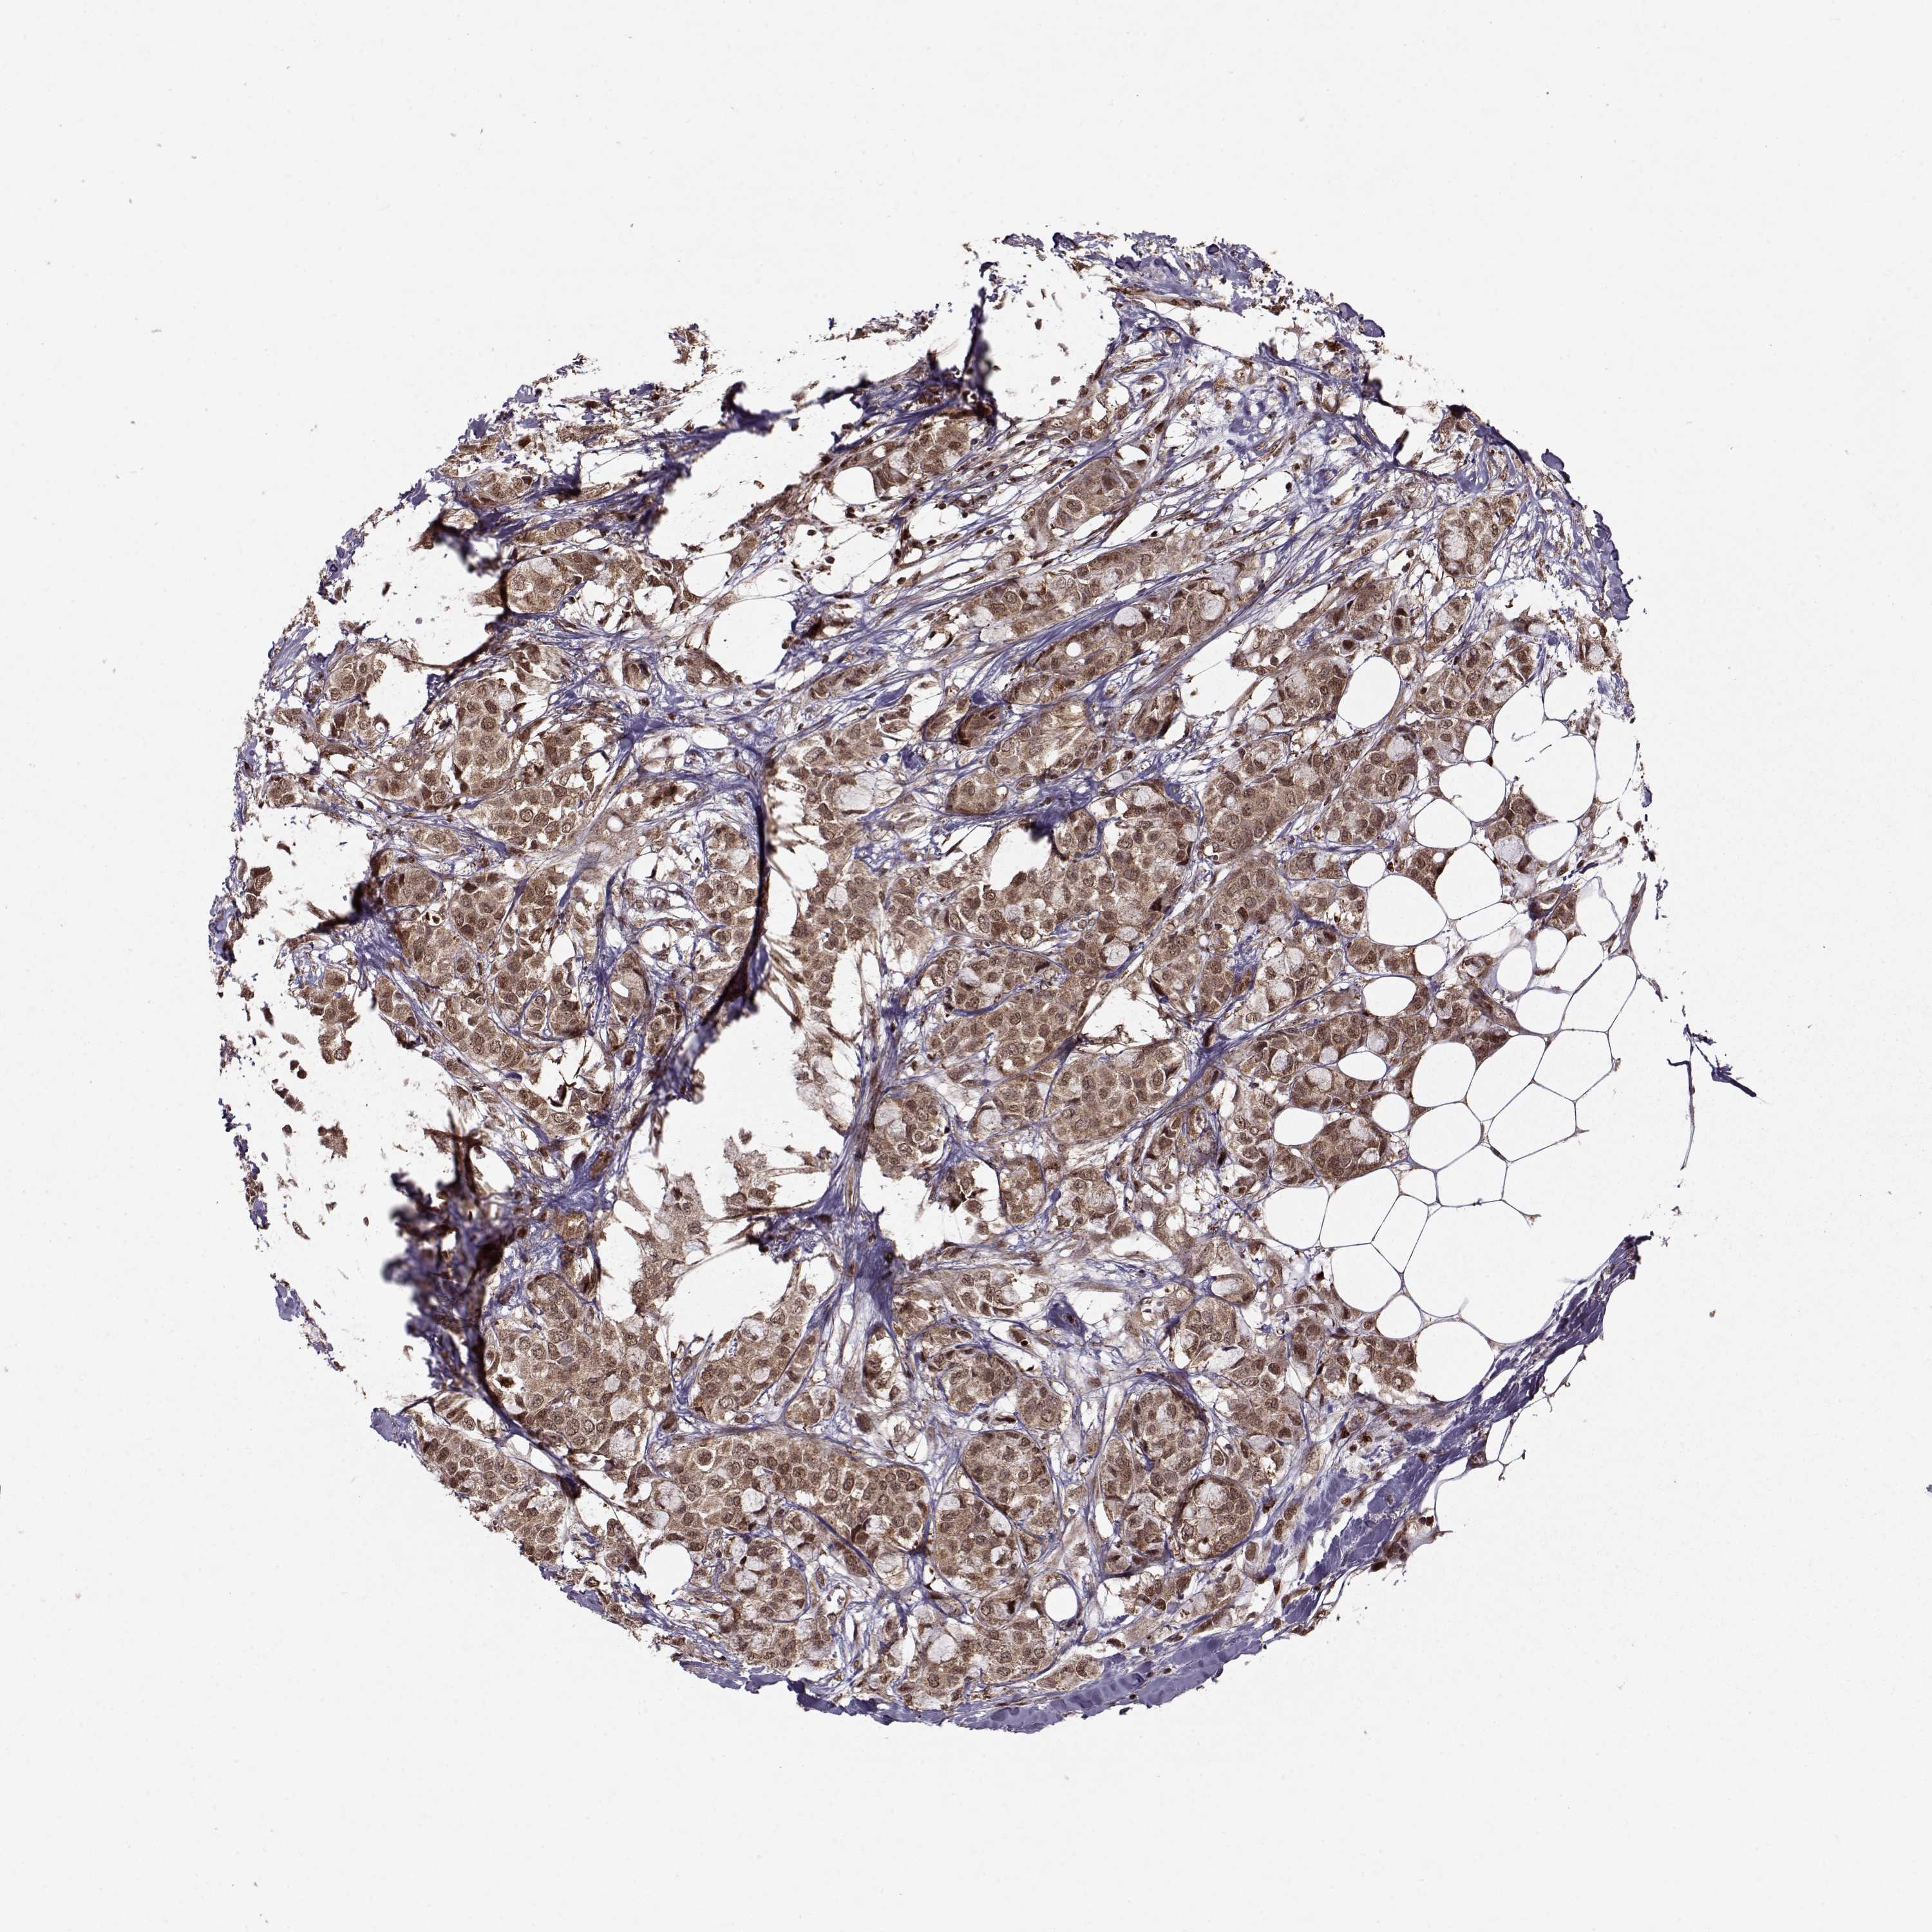

CANCER BREAST CANCER Show tissue menu

BRCA TCGA BRCA VALIDATION PROTEIN EXPRESSION

ANTIBODIES

AND

VALIDATION